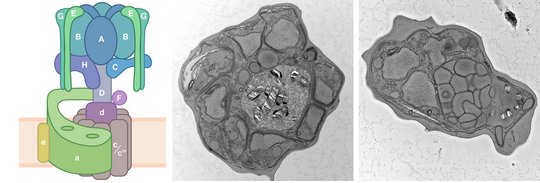

To ensure their survival in the human bloodstream, malaria parasites degrade up to 80% of the host erythrocyte hemoglobin in an acidified digestive vacuole. Here, we combine conditional reverse genetics and quantitative imaging approaches to demonstrate that the human malaria pathogen Plasmodium falciparum employs a heteromultimeric V-ATPase complex to acidify the digestive vacuole matrix, which is essential for intravacuolar hemoglobin release, heme detoxification, and parasite survival. We reveal an additional function of the membrane-embedded V-ATPase subunits in regulating morphogenesis of the digestive vacuole independent of proton translocation. We further show that intravacuolar accumulation of antimalarial chemotherapeutics is surprisingly resilient to severe deacidification of the vacuole and that modulation of V-ATPase activity does not affect parasite sensitivity toward these drugs.